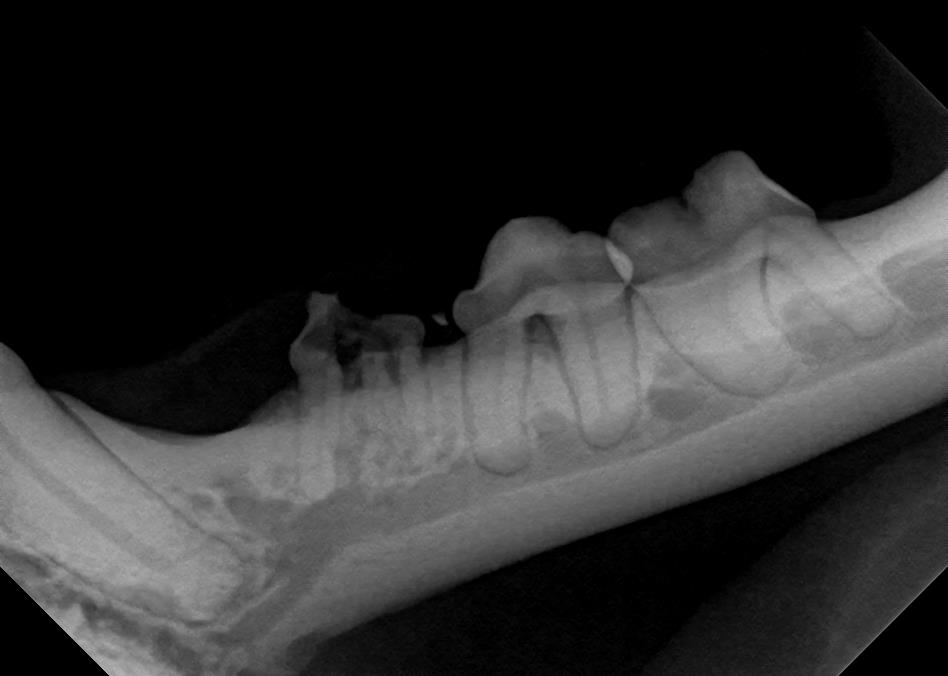

Dog and cat dental cleanings are not complete without full mouth X-rays. Though in many cases, the visible crown of the tooth may appear normal, Dental Radiographs can reveal problems with the root below. Once all of the teeth have been X-rayed, our veterinarian will review them and decide what treatment, if any, is required for each tooth. At Angel Oak Animal Hospital, all dog and cat dental cleanings include full mouth radiographs. If you would like more information about our Dental Radiographs services, call us at (843) 779-9669 or (843)559-1838 to schedule an appointment today.

Dental radiographs (X-rays) are an important part of evaluating your pet’s oral health. Because pets cannot stay completely still or follow instructions during the procedure, these images must be taken under general anesthesia. Anesthesia ensures your pet remains comfortable, safe, and still enough for us to capture clear and accurate images. Dental Radiographs are safer than ever for pets and humans alike, with minimal exposure to radiation, which is completely harmless.